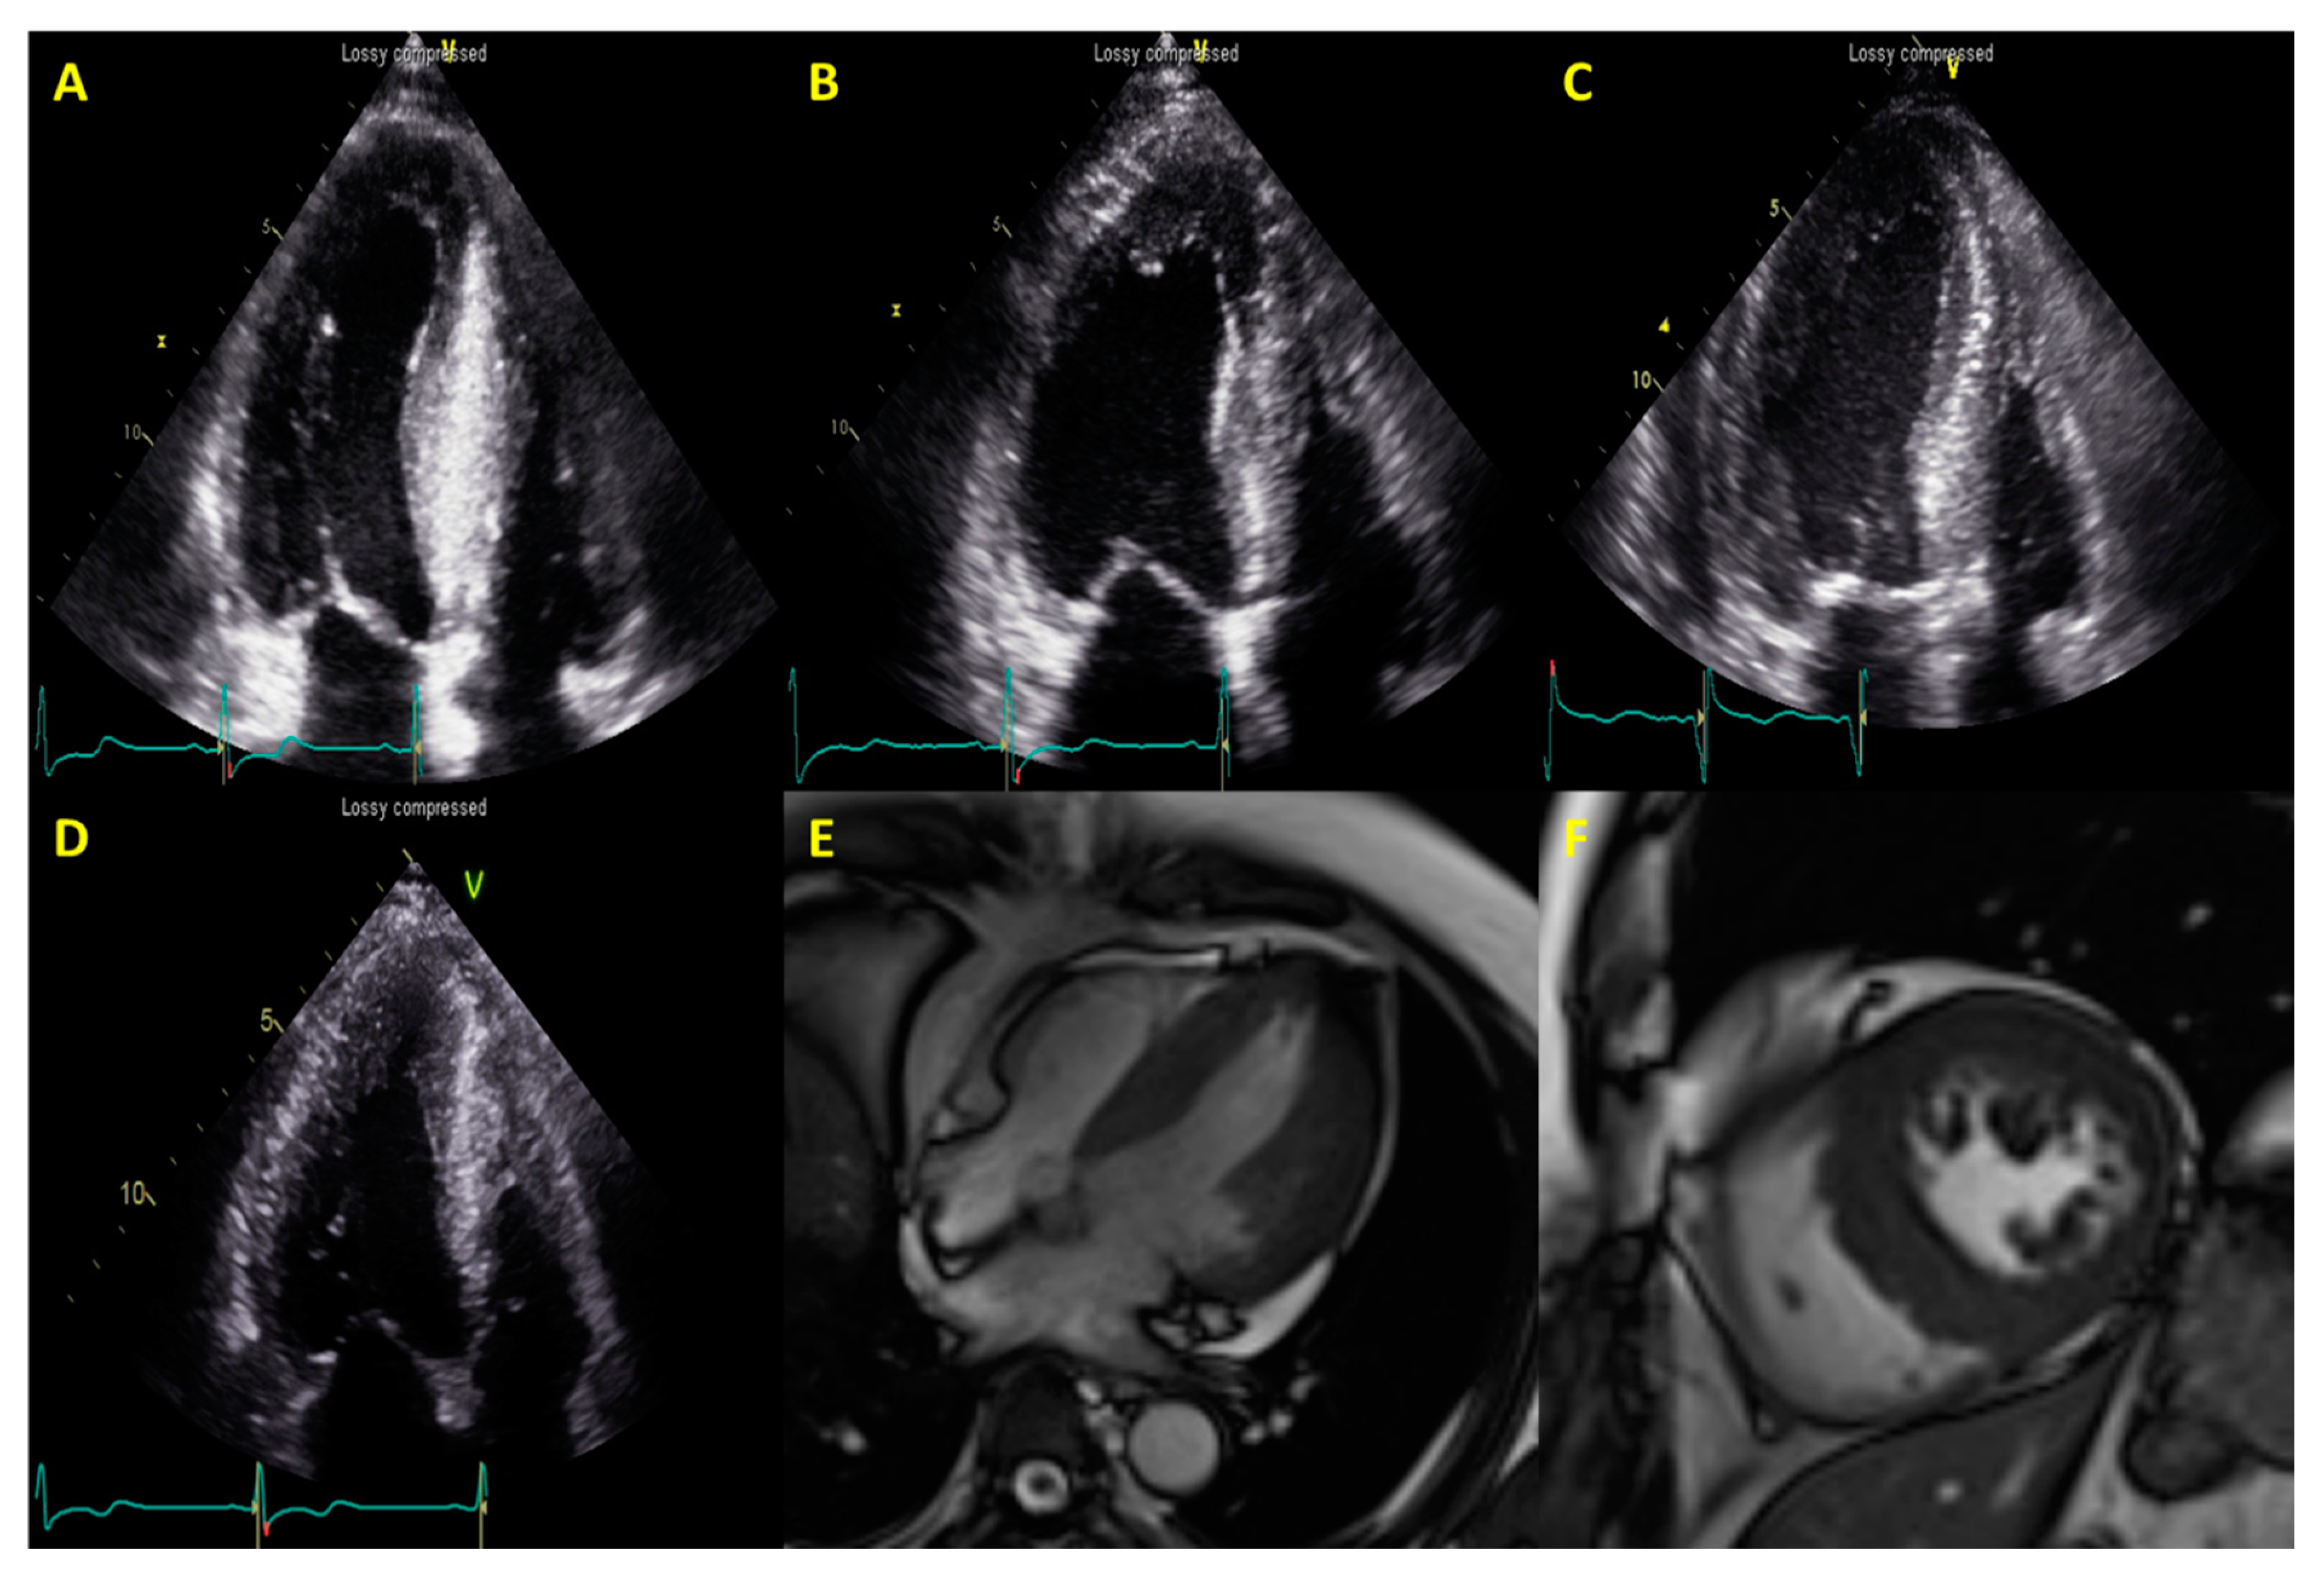

| CMR findings | |||

| Presence of LGE | 51 (92.7) | 26 (76.5) | 0.029 * |

| LGE volume (mL) | 13.4 ± 12.5 | 11.0 ± 11.7 | 0.159 |

| LGE volume percent (%) | 9.12 ± 6.7 | 6.06 ± 4.9 | 0.021 * |